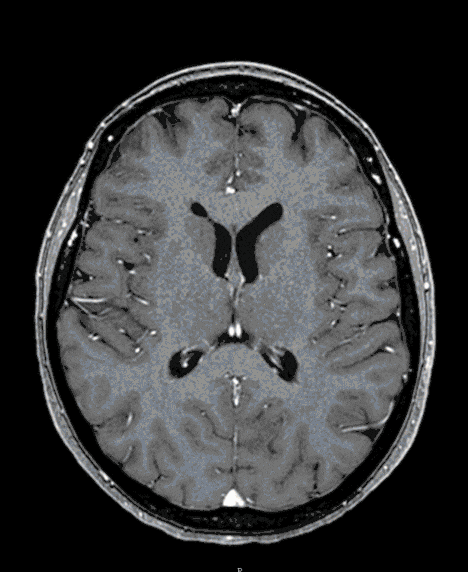

Skull base meningioma

Skull-based meningiomas are mostly benign tumors that can grow considerably due to their nature and slow growth. They threaten the function of the brain and its exiting nerves (cranial nerves of the brain stem).